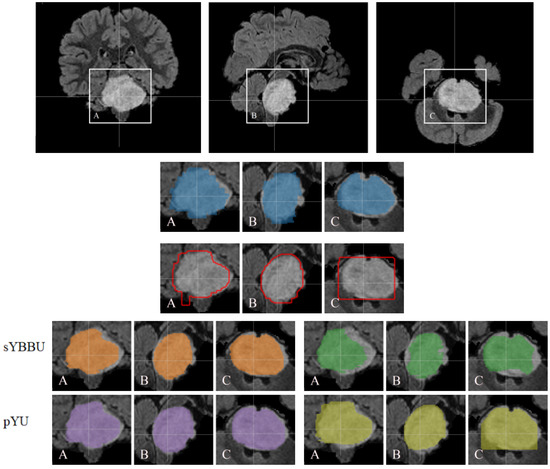

Furthermore, bounding-boxes also have a positive effect when they are used as inputs in the BB-UNet models. There is an increase in mean precision and a decrease in standard deviations of precision and Dice index. After masking, the results of UNet and BB-UNet are very similar, with BB-UNet coming slightly ahead, with an improvement in precision between 1% and 3%, and a recall that remained similar among all the models. Figure 3 exhibits clearly that models using the bounding-boxes perform better, especially sYBBU models. To compare the sYBBU model as the best approach using bounding-box with UNet that ignores them, we computed the AUC of the mean precision-recall graph. We obtained 0.91, 0.90 and 0.93 on the FLAIR, T2w and ens.(FLAIR, T2w), respectively, on the sYBBU model. Meanwhile, on the UNet model, we obtained 0.80, 0.83 and 0.90 using the FLAIR, T2w and ens.(FLAIR, T2w), respectively.

Table 6 shows the segmentation results obtained on the LGG t e s t dataset. Overall, the proposed models exhibit comparable results with those obtained on the TCGA-GBM t e s t dataset but show an average drop in the Dice metric of 0.05. This reduction was expected since the networks were solely trained on High Grade Gliomas and were not readapted for the Low Grade Glioma cases. Unlike the proposed models using bounding-boxes, UNet showed poor performance on the LGG t e s t dataset. However, the pYU model shows an improvement in the overall results by increasing precision by 30% at the cost of a mean decrease of 10% of the recall. We obtained an AUC score of 0.80, 0.87 and 0.89 for the FLAIR, T2w and ens.(FLAIR, T2w), respectively, when using the sYBBU. Comparatively, we obtained an AUC score of 0.71, 0.73, 0.80 for the FLAIR, T2w and ens.(FLAIR, T2w), respectively, when using UNet only. See also Supplementary Figure S4.

Figure 3. Mean precision-recall graphs of the different proposed segmentations on the TCGA-GBM t e s t dataset. To focus on the most interesting part of the plot, we only plotted the precision-recall scores for thresholds between 0.1 and 0.9. From the left to the right, Using the FLAIR, using the T2w, and ens.(FLAIR, T2w).